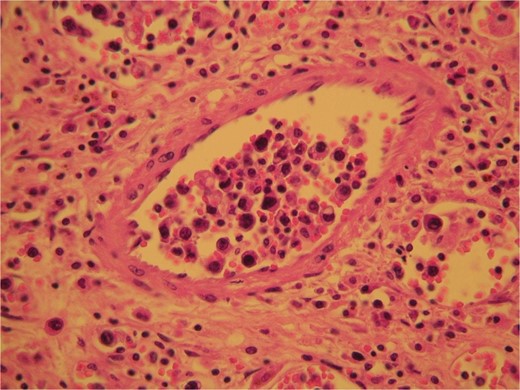

Histologic sections

The surgical specimen consisted of a solid, soft, tan colored 10.5 × 7 × 4 cm tumor (Fig. 2). H&E sections showed a neoplasm confined to the adrenal gland consisting of tumor cells located inside dilated, thin-walled vascular spaces (Fig. 3). The neoplastic cells were large with irregular nuclei that exhibited atypia and had one or more nucleoli. Necroses were evident. Immunohistochemical stains showed that the neoplastic cells were positive for Vimentin, LCA, CD20 (Fig. 4), CD79a (Fig. 5) and negative for Cyrokeratins 7, 8, 18, 19, HMB45, S100, CD30, Myeloperoxidase, Inhibin, CD3, CD5, CD56, Chromogranin, CD31 and CD34. These findings were consisted with the diagnosis of primary adrenal intravascular large B-cell lymphoma. The patient was then referred to a Hematology Unit for further staging and treatment. Six cycles of R-CHOP were given lasting 21 days each: (Rituximab 375 mg/m2 iv (D1), Cyclophosphamide 750 mg/m2 iv (D1), Doxorubicin 50 mg/m2 iv (D1), Vincristine 1 mg/m2 iv (D1), P: Prednizolone 100 mg iv on D1-D5). After the completion of this chemotherapeutic regimen, a PET scan showed complete remission of the disease. Thereafter, the follow-up schedule consisted of CT studies every 6 months for 2 years and once annually, for the next 3 years. Despite the dismal prognosis, the patient 6 years after the initial diagnosis remains alive and in complete remission.

H&E sections revealed the presence of tumor cells inside dilated, thin-walled vascular spaces exhibiting minimal cytoplasm and irregular nuclei with atypia.